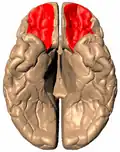

![]() Orbital surface of left frontal lobe (from below) | |

-

Orbital gyrus shown in red -

Basal surface of cerebrum. Orbital gyrus shown in red. -